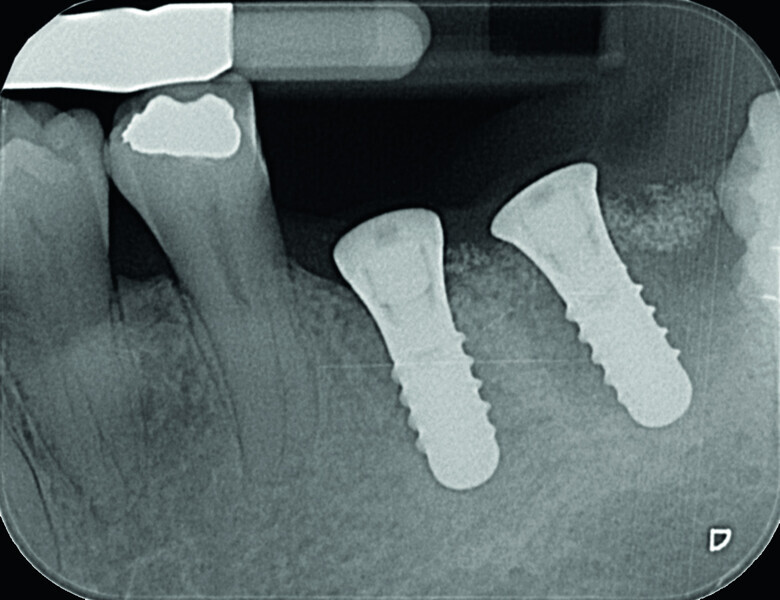

Digitising your implant practice